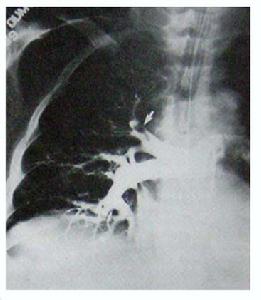

其他輔助檢查:用力肺活量哮喘患者由於患病時間長對症狀出現耐受,呼吸功能的客觀檢查對病情評估尤其重要。分別在臨睡前、夜間覺醒後和清晨時以峰速儀動態測定最大呼氣流量(PEF),同時在午後測定PEF以確定一天中最佳的呼吸功能狀態作為比較基礎值。通過峰速儀的動態觀察,可以了解哮喘狀態,採取正確的處理,可以避免就診時一次測定造成的錯誤判斷,因此應對白天和夜間狀態進行全面評估,同時當患者處於穩定期,動態峰速儀監測常可提示病情變化,應及時提醒病人。通常哮喘患者出現急性發作,可在數天前就有PEF逐漸下降,PEF的變異幅度增大,可及時就診或加以處理。對疑及有睡眠暫停綜合徵者則需進行夜間睡眠監測。